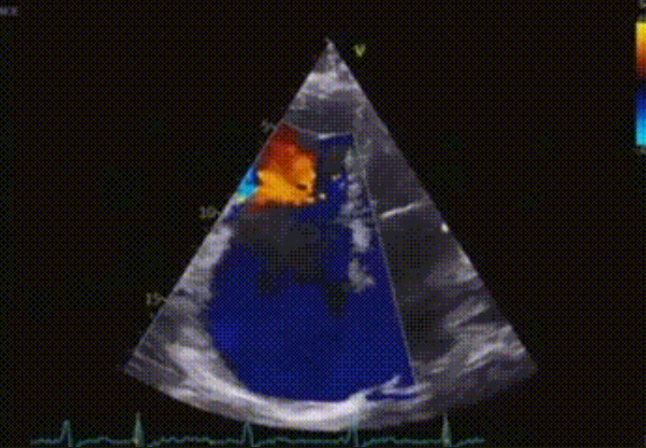

術(shù)前心臟超聲提示:極重度三尖瓣返流,右房容積明顯增大,三尖瓣瓣環(huán)顯著擴張。

術(shù)后心臟超聲提示:LuX-Valve Plus植入后,三尖瓣瓣環(huán)處可見人工瓣膜回聲,未見返流,人工瓣膜穩(wěn)定,瓣葉開閉良好,連續(xù)多普勒估測三尖瓣平均跨瓣壓差僅為1mmHg。